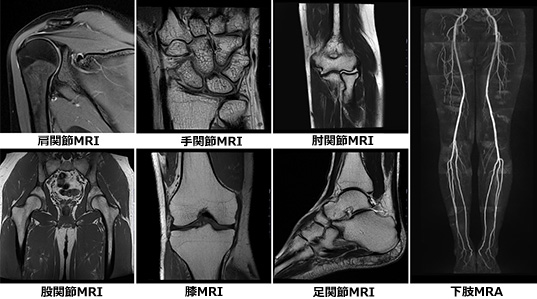

ドイツ シーメンス社製の最新鋭MRI装置「MAGNETOM Lumina」を導入しています。

AIを用いた画像再構成技術を使用することで、質の高い画像を提供することができ、高速撮影技術を用いてこれまでの装置よりも検査時間を短縮することが可能になりました。

また、従来よりボア経が約10cm広くなったことにより撮影時の圧迫感軽減ができるなど、患者さんにとって一番負担の少ない体勢を選択して検査を行うことができます。

Signa HDxt 1.5T

最新鋭器に更新することにより、これまで以上に高画質の撮影が可能となりました。また、これまでにはできなかった、新たな画像も撮影できるようになり、日常臨床に役立てています。